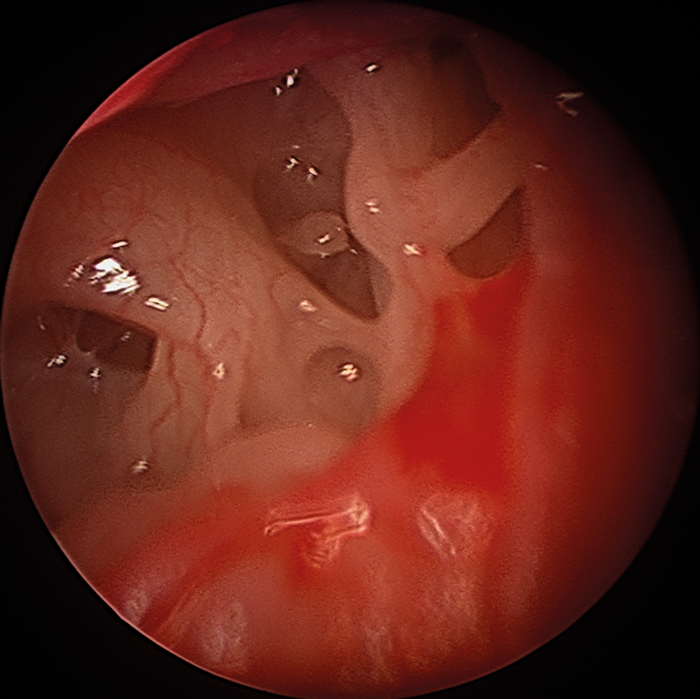

Angled endoscopes and instruments allow retro-tympanic dissection under direct vision so are ideally suited, whether used for TEES or through a post auricular incision. Using a front-to-back technique with TEES, cholesteatoma can be followed as far back as the mastoid antrum to the limits of the lateral semicircular canal (Figure 3). It is appropriate to reconstruct the canal wall defect to prevent recurrent disease, but in younger children, it is unlikely that the tragus will provide sufficient cartilage, especially if pars tensa reconstruction is also required. Careful consideration must be given between the merits of TEES in such cases or a conventional canal wall up procedure.

Figure 3. Pars flaccida cholesteatoma of the right ear in a 14-year-old (left panel) which extended into the mastoid antrum. Attico-antrostomy was completed totally endoscopically using a bone curette (centre). Close-up view with a 45° endoscope after KTP laser showing the lateral semicircular canal as the inferior and posterior limit of the dissection, and the short process of the incus anteriorly (right). As the pars tensa was normal, adequate tragal cartilage was available for canal wall reconstruction at this age.